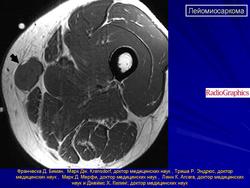

Лейомиосаркома.

High-grade leiomyosarcoma in the left thigh

Рисунок 15.5

Рисунок 15.6.